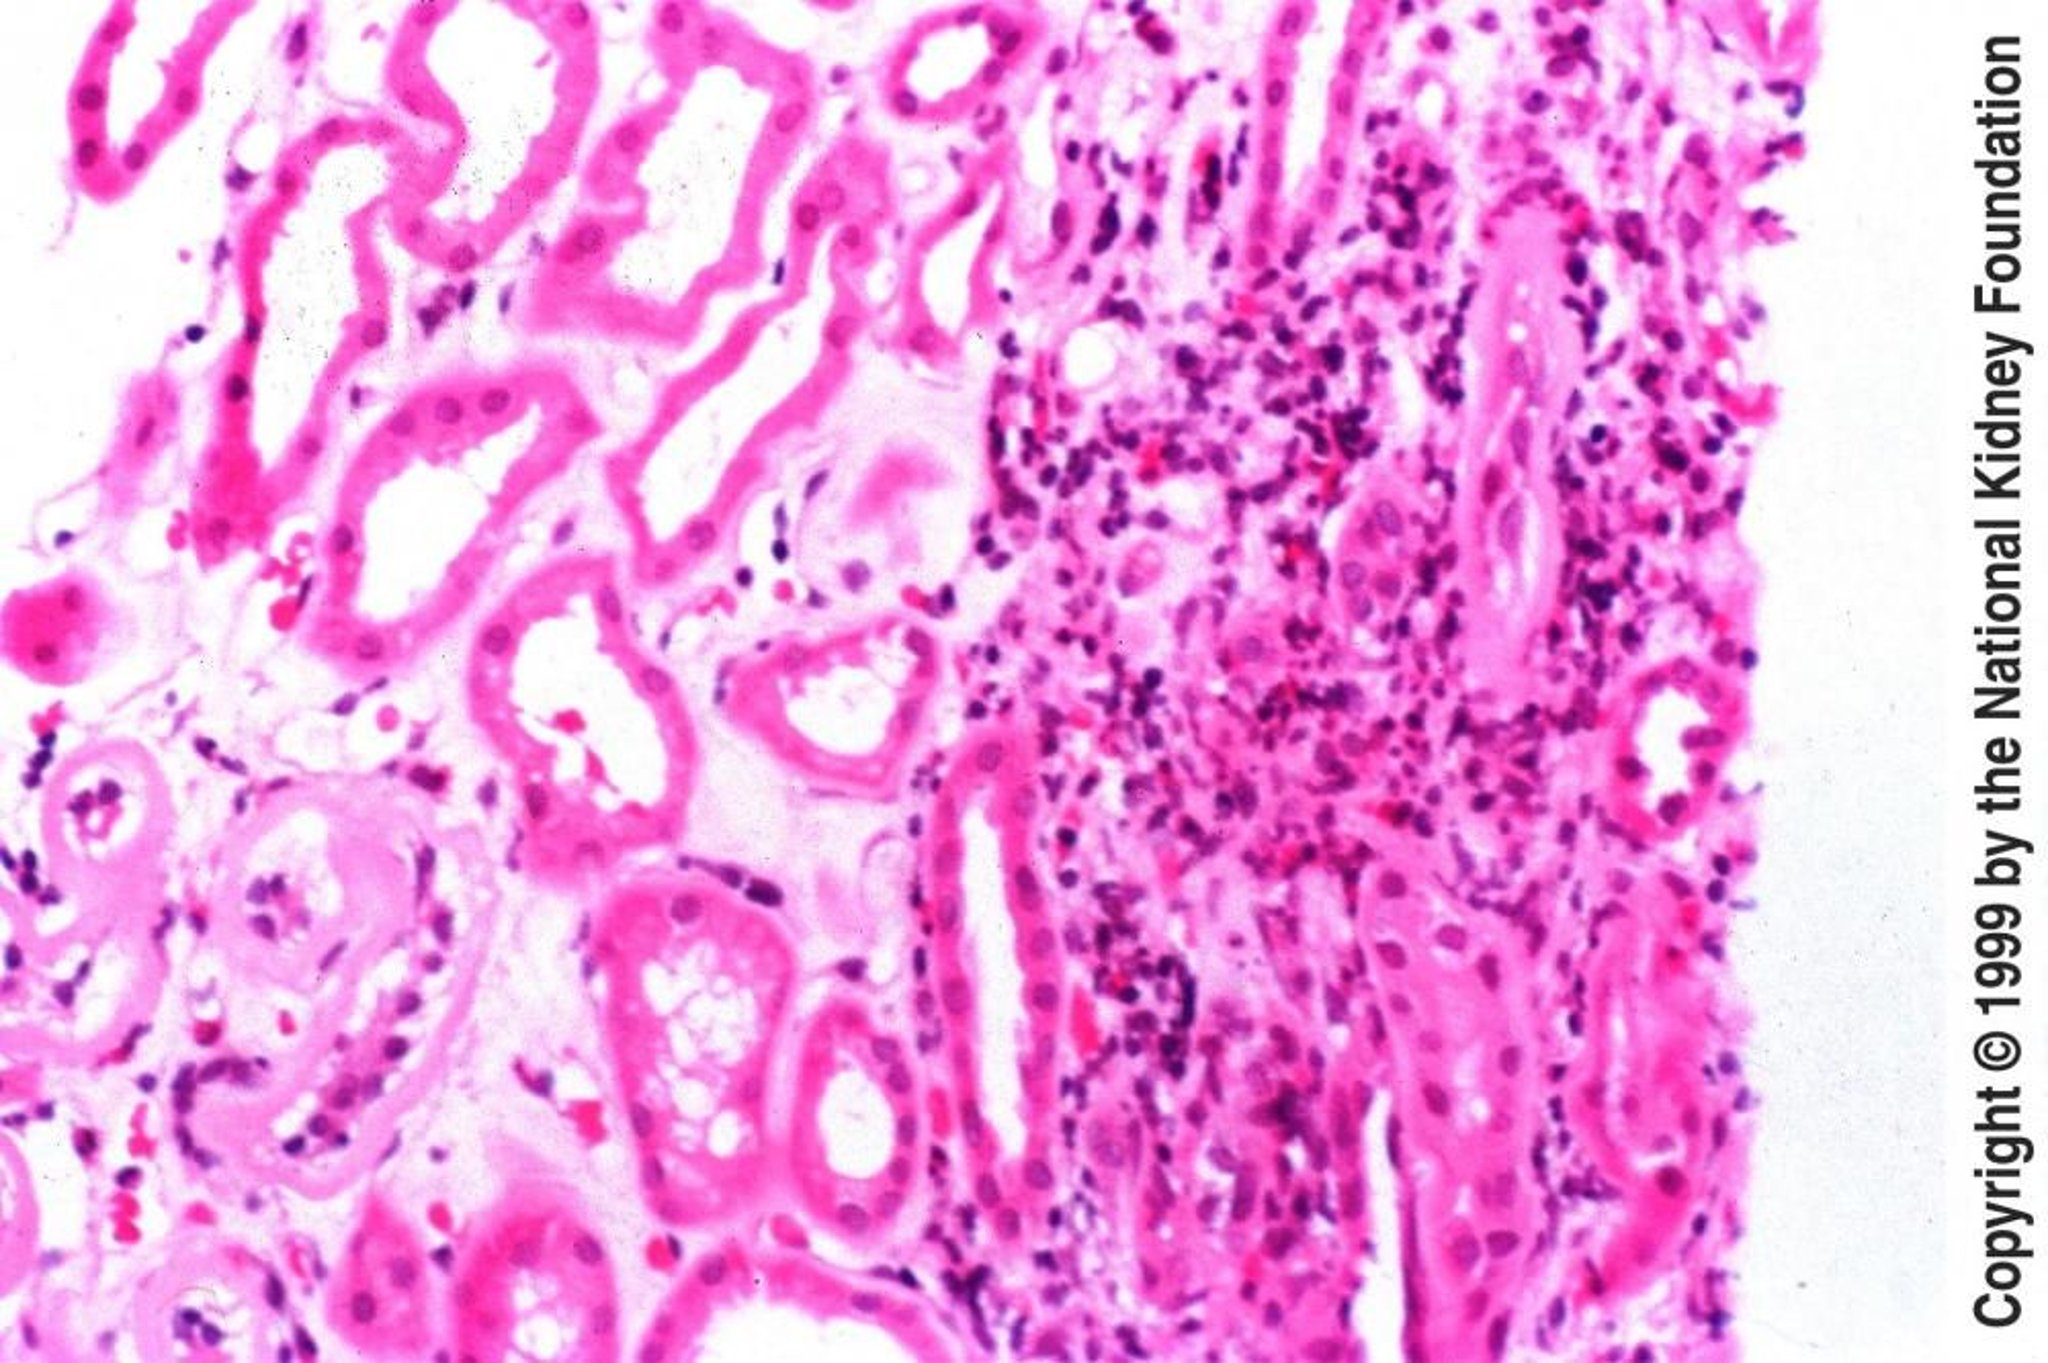

Néphrite tubulo-interstitielle aiguë

La biopsie dans la néphrite tubulo-interstitielle aiguë montre un œdème interstitiel avec infiltration par des éosinophiles, des lymphocytes et des plasmocytes (coloration à l'hématoxyline-éosine, ×200).

Image fournie par Agnes Fogo, MD, and the American Journal of Kidney Diseases' Atlas of Renal Pathology (voir www.ajkd.org).